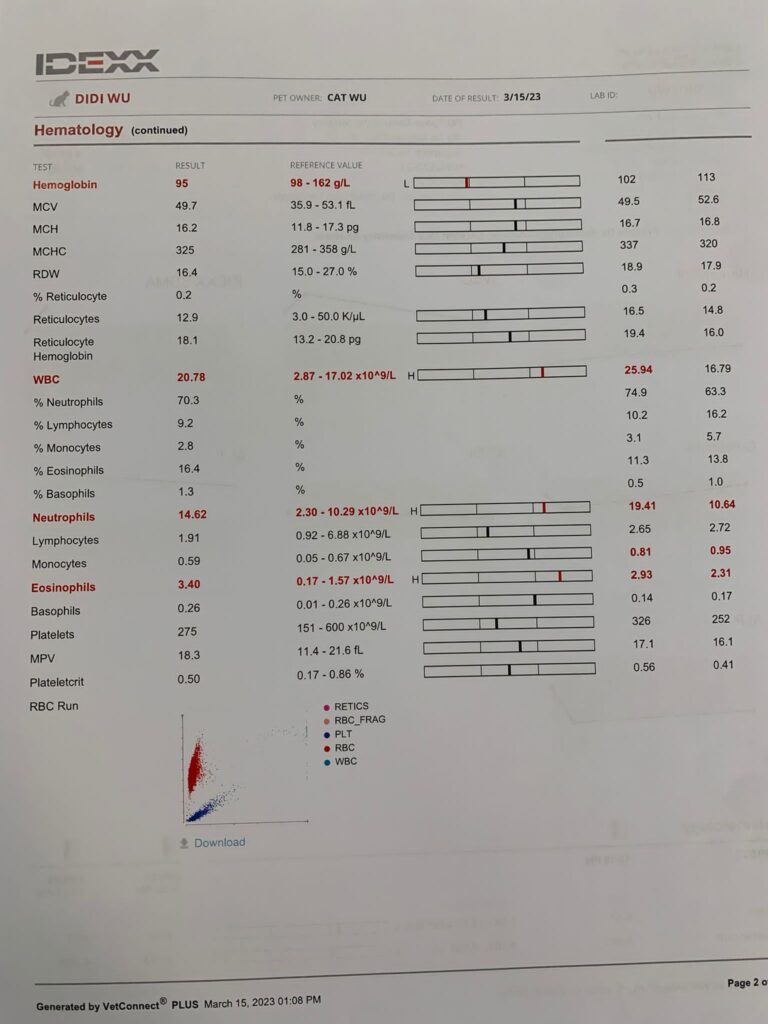

Cbc out: Eos high again – dr wants him to be dewormed. Hct 26.9%, going up, wbc 20.35 going down doxy to continue for total 21 days.

Morning: bring didi go dr nally review. 4.28kg – lose 60g in 2 days. Cbc taken. HCT up to 30.4%, EOS even higher. Reject doing liver panel. Nothing significant. Just tell me to finish up the 14 days Clav then can stop (till 2.7) Drontal n review every 2-3 months. I’ll decide again Re the allergy jabs.

HCT 29.5%, dr nally say she don’t like her EOS 3.24, but it’s a gone down figure cos March he had fenbendazole alr. Will tell them deworm him today. Alt 177 – continue ornipural. GGT 6, restart ursofalk 65mg. 15mg/kg in short. add on Clav 14 days, 0.22ml and anti histamine jabs (expire dec 23) – price $188 don’t make sense so didn’t buy.

Cbc Chem10 done. His blood is soooo dark red. yet 29% only!?

stop ab – neu glob wbc all not much improvement. And mos Eos thingy elevated – can be due to some cancer thingy. but that will be eos 40, but didi Eos is 4+.

Still can feel the enlarge spleen and liver enlarge too – so retake Chem 10

HCT 29.2%, Erm drop leh. (Semintra loh) – but have to continue (UPC 0.43) and Clav have to continue

Cbc looks fine. Omg the price of Cbc so ex here. NEU EOS high, I’m happy actually – better than Low. Thought is like xiao Hui false alarm, can survive de!!! TP 10.5, glob 7.5. dr d didn’t mention he needs any ab at all.